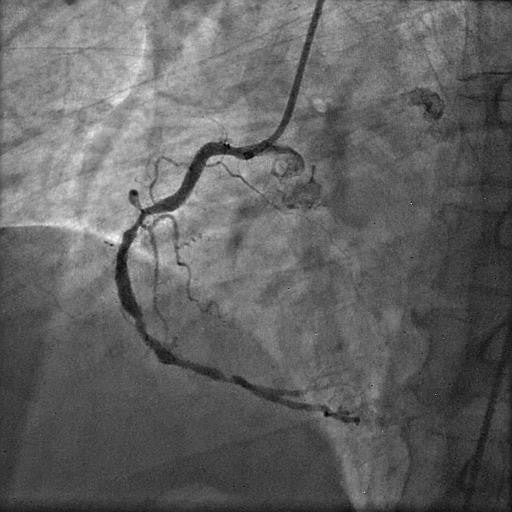

Picture 2: Diagnostic right coronary angiogram showing dominant vessel with extensive calcification and significant stenotic disease involving the proximal, mid, and distal segments

There was significant ostio-proximal disease in both the LAD and LCx, along with total proximal occlusion of the OM branch. Right coronary angiography demonstrated a dominant vessel with extensive calcification and significant stenotic disease involving the proximal, mid, and distal segments.